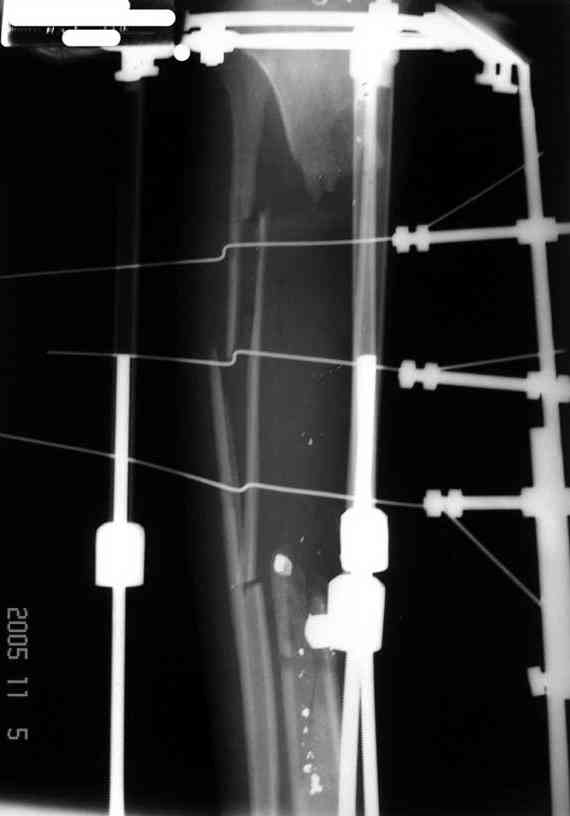

Отправлено Ласунский Сергей 30 Октябрь 2007, 23:53 РОСНИИТО им.Р.Р.Вредена

Пациентка с дефектом большеберцовой кости, возможно ли восстановление опороспособности нижней конечности? ДТП 1.5 года назад: открытый оскольчатый перелом средней трети левой голени с дефектом мягких тканей. Выполнены следующие операции в одной мз больниц города: 1.При поступлении ПХО и наложение АВФ 2.Нагноение резекция нежизнеспособной кости. 3.Пластика дефекта мягких тканей. 4.Попытка устранения дефекта по методу Илизарова, нагноение, радикальная хирургическая обработка, увеличение дефекта. 6 месяцев без признаков гнойного воспаления. В настоящее время иммбилизация гипсовой лонгетой до коленного сустава, функция коленного сустава сохранена, голеностопного нет.

Уважаемый Александр! Привет из Питера. Спасибо за быстрый ответ. Стержень с блокированием и кейдж, вариант изветный по литеоатуре, но очень короткий дистальный фрагмент и локальный остеопороз (будет ли хорошая фиксация?). Как считаешь вариант с фиксацией ложного сустава малоберцовой кости спластиной и ее предварительное утолщение свободным аутотрансплантатом 1\2 малоберцовой кости со здоровой стороны длиной 20-25 см., а после консолидации тибиализация малоберцовой кости?

учитывая имеющиеся диагноз (хр.рецидивир.остеомиелит) испольхзование погружных методов,тем более на голени,очень сомнительно ( зря выкините деньги) лечим такие вещи в АВФ с фиксацией смежных сегментов полилокальным остеосинтезом. В данном случае в принципе возможно перепилить не только проксимальный фрагмент,но и дистальный, можно комбинировать все это дело с тибиализацией малоберцовки ( как уже предлогалось выше). У меня есть опыт замещения подобного дефекта на протяжении 25см.Дерзайте, в любом случае пациентка уже ничего не теряет.